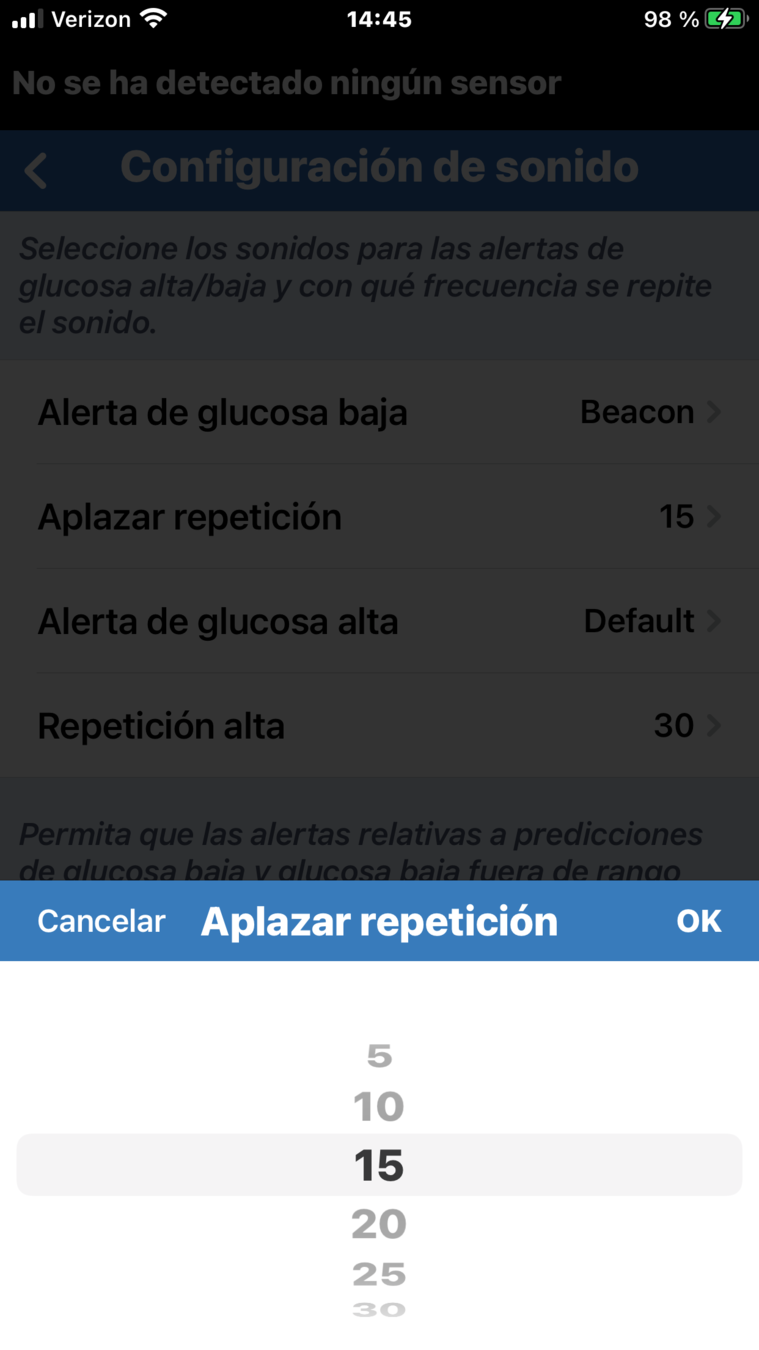

FUNCIÓN DE REPETICIÓN DE ALERTAS

La función de repetición de alertas

le permite definir la frecuencia con

la que le gustaría que se repita una alerta.

Basta con tocar la opción de repetición.

FUNCIÓN DE REPETICIÓN DE ALERTAS

Desplácese para definir el tiempo. A continuación, toque OK.

La función de repetición de alertas

le permite definir la frecuencia con

la que le gustaría que se repita una alerta.

Basta con tocar la opción de repetición.

FUNCIÓN DE REPETICIÓN DE ALERTAS

En este ejemplo, en el que el ajuste de repetición de alerta de glucosa baja está definido en 15 minutos, el usuario recibirá una alerta de glucosa baja cada 15 minutos siempre que el nivel de glucosa permanezca por debajo del umbral de alerta de glucosa baja.

La función de repetición es una característica importante que debe entender si considera que debe

ajustarse la frecuencia con la que

recibe las alertas.

FUNCIÓN DE REPETICIÓN DE ALERTAS

En este ejemplo, en el que el ajuste de repetición de alerta de glucosa baja está definido en 15 minutos, el usuario recibirá una alerta de glucosa baja cada 15 minutos siempre que el nivel de glucosa permanezca por debajo del umbral de alerta de glucosa baja.